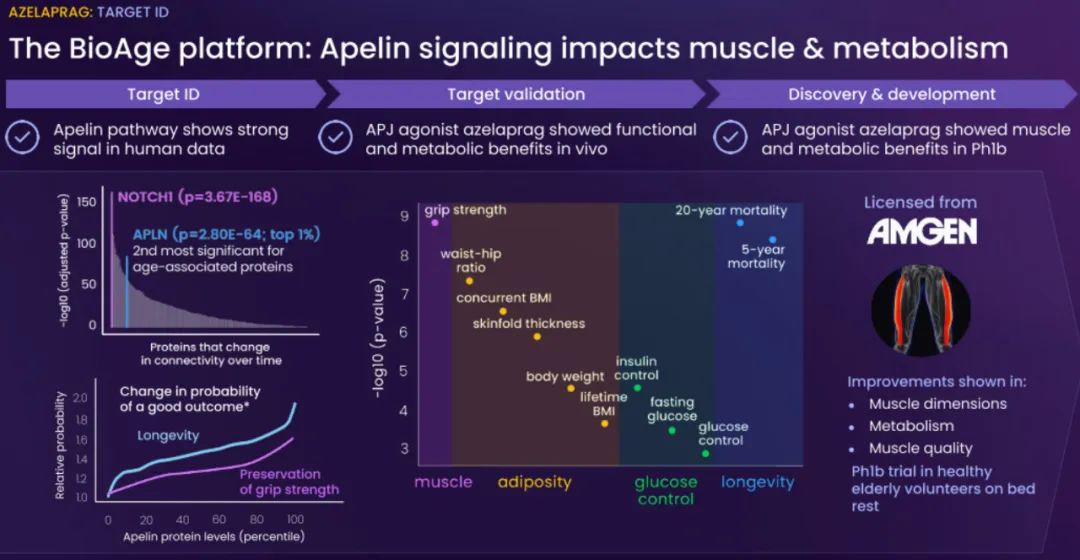

BioAge Labs的主要关注点是代谢疾病,这是全球最大的医疗保健挑战之一。BioAge Labs的主要候选产品 Azelaprag是一种口服小分子,在8个 1 期临床试验中,265 名受试者的耐受性良好。在临床前肥胖模型中,azelaprag 显示出能够使胰高血糖素样肽-1 受体 (GLP-1R) 激动剂诱导的体重减轻增加一倍以上,同时恢复健康的身体成分并改善肌肉功能。

这些临床前结果得到BioAge Labs在卧床老年人中进行的 1b 期临床试验的支持,在该试验中,BioAge Labs观察到在 10 天内接受 azelaprag 治疗的受试者的肌肉萎缩减少、肌肉质量保持良好并且新陈代谢得到改善。